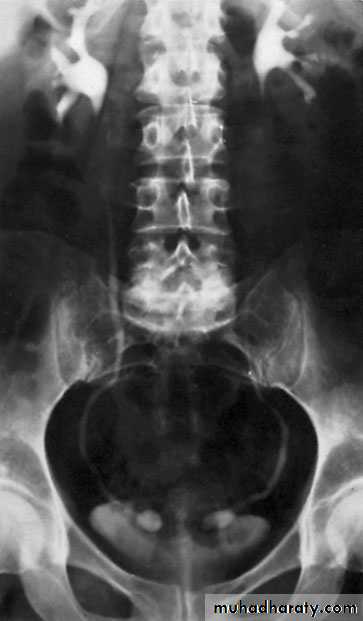

Crossed Renal Ectopia With and Without FusionHorseshoe Kidney

found in 1:1000 necropsies an is commoner in men.probably the most common of all renal fusion anomalies

The anomaly consists of two distinct renal masses lying

vertically on either side of the midline and connected at

their respective lower poles by a parenchymatous or fibrous

isthmus that crosses the midplane of the body.

Fusion of the renal masses early in embryonic life, so its ascent

will be impeded by inferior mesenteric artery.

The kidneys are low located, mal rotated and pelves lie anteriorly

Symptom When present, they are related to complications like hydronephrosis, infection, or calculus formation

Diagnosis ultrasound, IVU, CT scan

Treatment:

-Medical: pain relief and to control infection-Surgical: stone removal, PUJ stenosis correction and isthmus division in cases of

-operations on the aorta

Prognosis usually they have normal life.